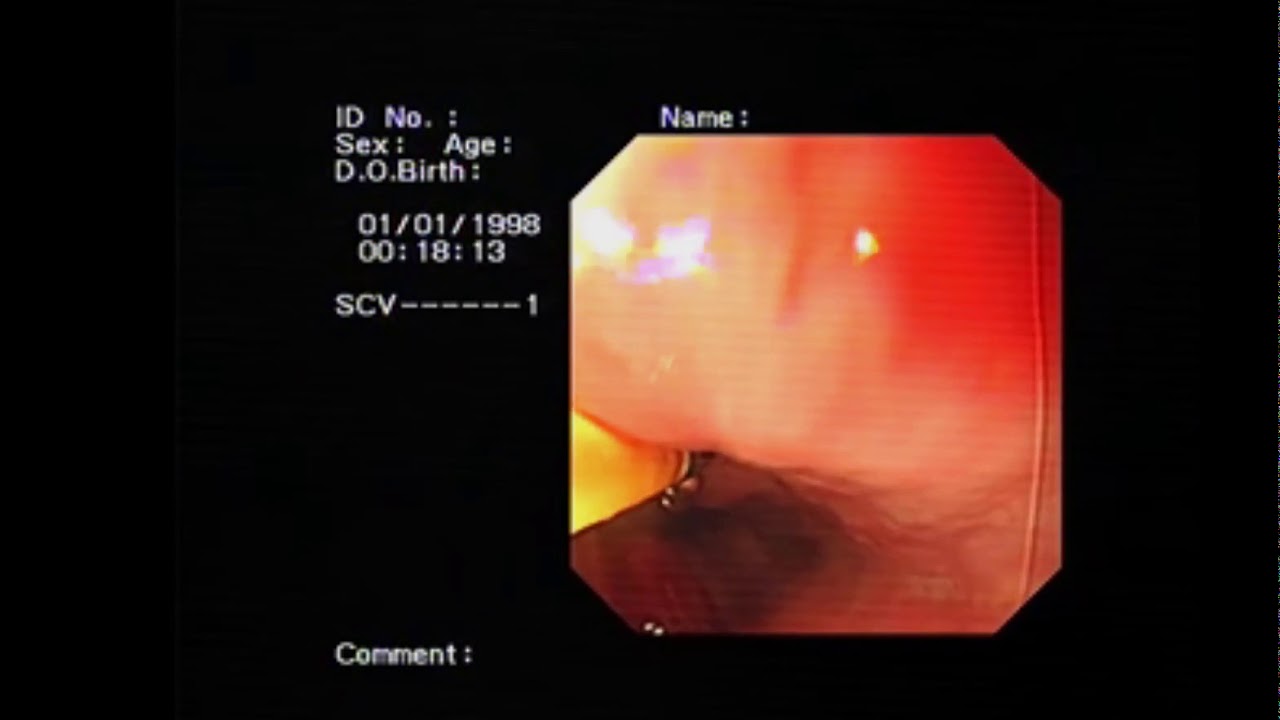

A 26-year-old man presented to our hospital with persistent epigastric pain, and heartburn was admitted to our hospital. The patient gave a long term history of proton pump inhibitors use. Upper digestive endoscopy was undertaken. A spurter resulted from biopsies that were taken from the lower esophagus. What is your opinion 1- nothing, wait and see policy

2- intervene?